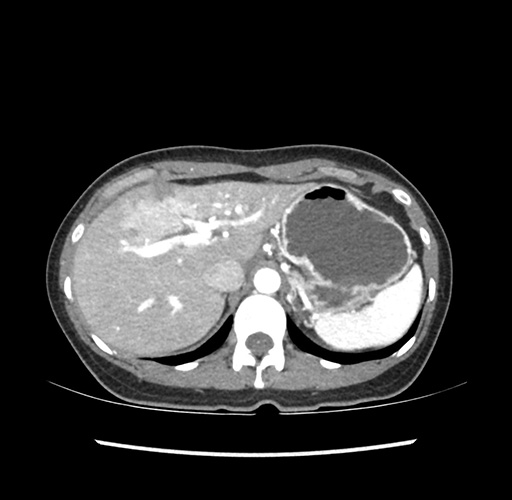

Imaging Analysis

Look through the patient's CT scan to identify any areas of concern for the necessary procedure.

Based on your CT findings, which issue(s) would give reason for "planned slowing down moment(s)" in this case?